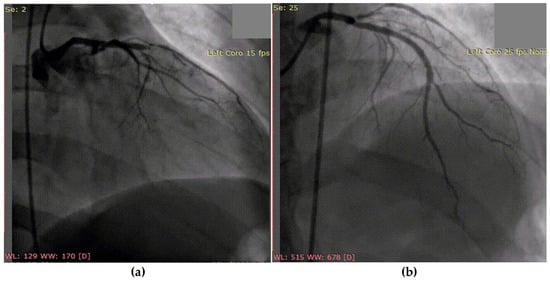

3.2. Case 2